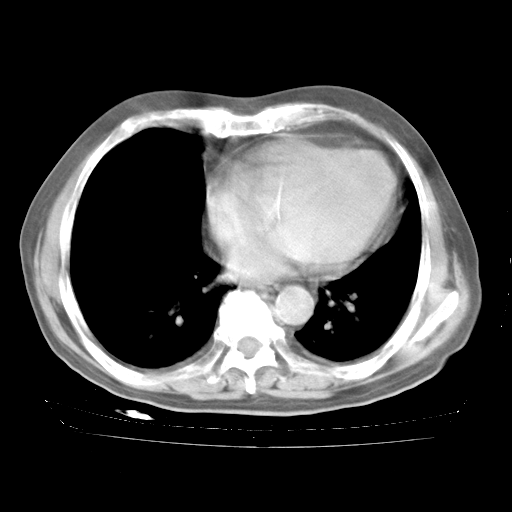

4月28日肺部CT——再次出现类似去年5月9日——透光度降低,“间质性”改变。

4月28日肺部CT——再次出现类似去年5月9日——磨玻璃样、间有“粟粒样”改变。

4月28日肺部CT

个人阅读4.14日肺部CT平扫:纵隔窗无异常,但肺窗示:双下肺内、后基底段有片絮状侵润影,部位以后基底段为著,以间质改变为主,呈急性肺泡炎征像,和首次住院影像学有相似之处。仅是个人读片,明日请相关专家再读片哈。其它建议同上。